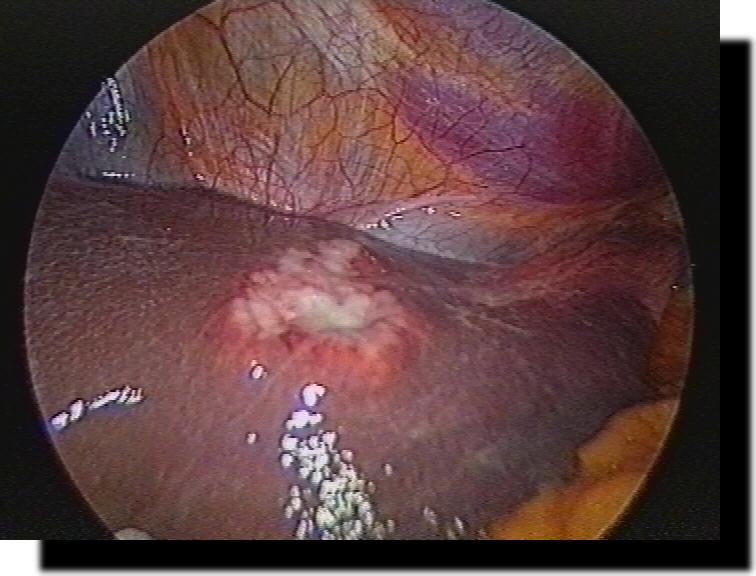

Akute Appendizitis